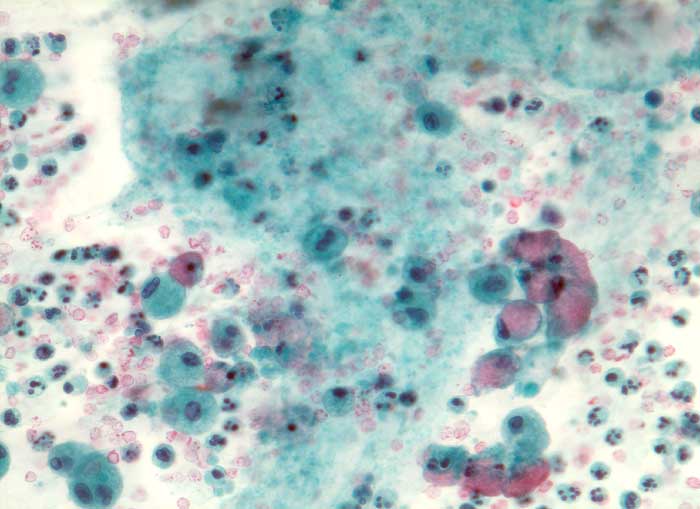

Die gut erkennbaren Zellgrenzen der hohen schlanken Zylinderzellen bilden bei Aufsicht ein Honigwabenmuster. Das Zytoplasma enthält eine grössere oder mehrere kleine apikale Schleimvakuolen, die den Zellkern zur Seite drängen. Das Chromatin ist fein granulär und regelmässig verteilt. Der Nachweis von Schleimbildung schliesst eine funktionelle Zyste aus. Metastasen von schleimbildenden Adenokarzinomen zeigen eine stärkere Kernpolymorphie und bilden keine regelmässigen Verbände.